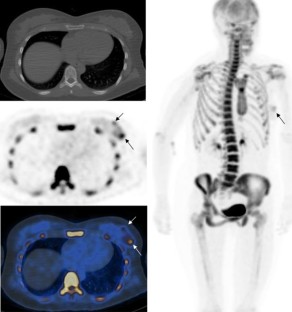

NaF positron emission tomography/computed tomography (PET/CT) images of 69 newly diagnosed breast cancer patients were reviewed. F-18 fluoride uptake as maximum standardized uptake value (NaF SUVmax) was measured in the primary tumor, enlarged axillary lymph nodes and contralateral normal/non-tumoral breast tissue. Low-dose CT images were reviewed to locate the primary tumor and grossly assess its calcification and check for ipsilateral axillary lymphadenopathy. Whole body NaF PET/CT images were reviewed to search for bone metastases. Eighteen patients also underwent F-18 fluorodeoxyglucose (FDG) PET/CT study.

Results

The primary breast tumor was clearly seen as focal or diffuse uptake on NaF PET images in 27 of 69 patients (39%) (mean NaF SUVmax: 2.0 ± 1.0). In the rest, there was only mild bilateral diffuse breast uptake. When analyzing images per histological subtype (42 patients, 43 tumors), 14 of 31 invasive ductal carcinomas (IDC) (45%) and 3 of 4 ductal carcinoma in situ (DCIS) were visible on PET. Five invasive lobular carcinomas, 2 invasive mammary carcinomas, and 1 mucinous carcinoma were not visible on PET. Mean NaF SUVmax of contralateral normal/non-tumoral breast tissue was 1.0 ± 0.4. There was no significant difference in mean NaF SUVmax of primary tumor in cases with and without calcification or with and without axillary lymphadenopathy (p 0.892 and 0.957). There was no correlation between NaF SUVmax and FDG SUVmax values of the primary tumors (r 0.072, p 0.797, Pearson correlation).